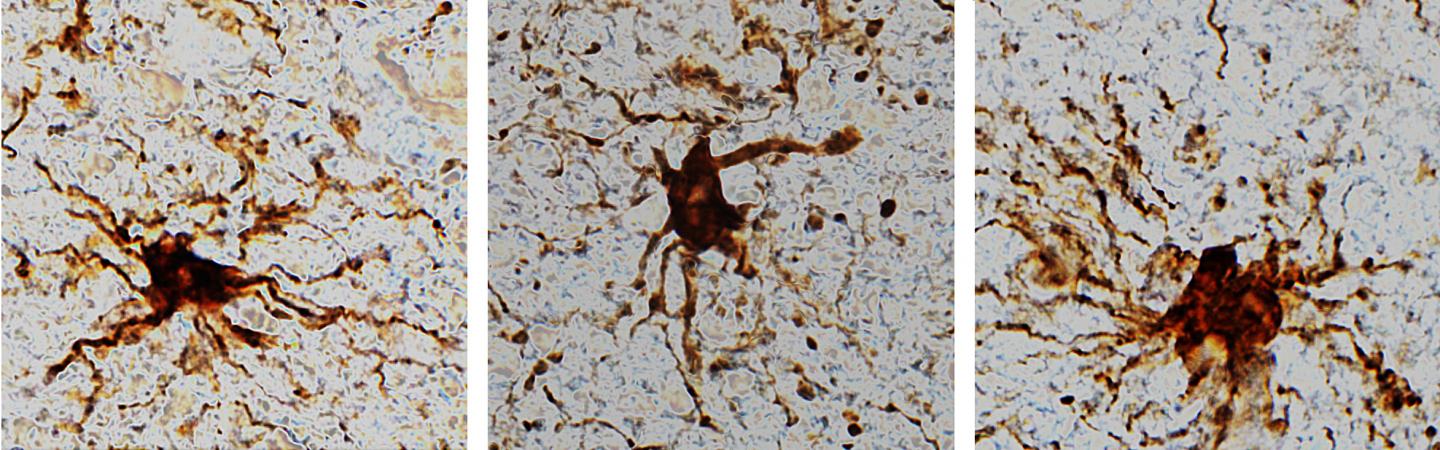

图片:“僵尸”细胞在人类大脑死亡后复活。资料来源:Jeffrey Loeb博士 UIC在我们死后的几个小时里,人类大脑中的某些细胞仍然活跃。根据伊利诺斯大